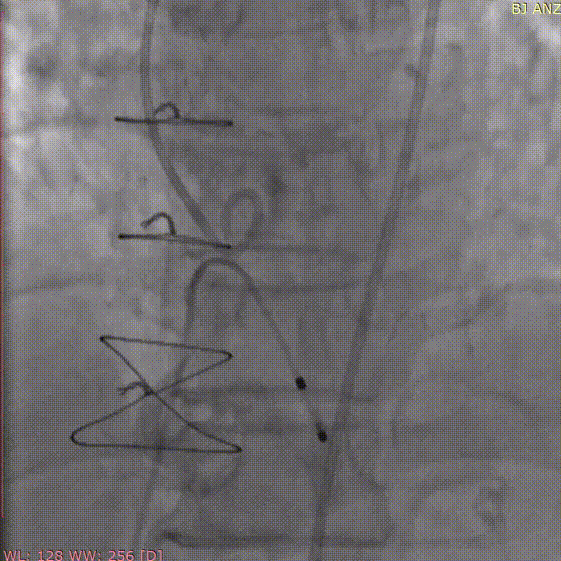

术前主动脉CTA评估:主动脉瓣三叶式,瓣叶基本等大,瓣叶稍增厚,左右瓣叶游离缘轻微钙化;主动脉瓣环周长折算直径约27.6mm;双侧冠脉开口高度可LCA:13.7mm,RCA:17.3mm;左侧冠脉轻度钙化;术中建议造影角度RAO:4°,CAU:22°;降主动脉及双侧髂总动脉轻微钙化,走行迂曲;双侧髂总动脉稍增宽;双侧髂外动脉迂曲。

右窦居中位:LAO:4° CAU:22°

主动脉瓣环夹角:44°

血管三维重建